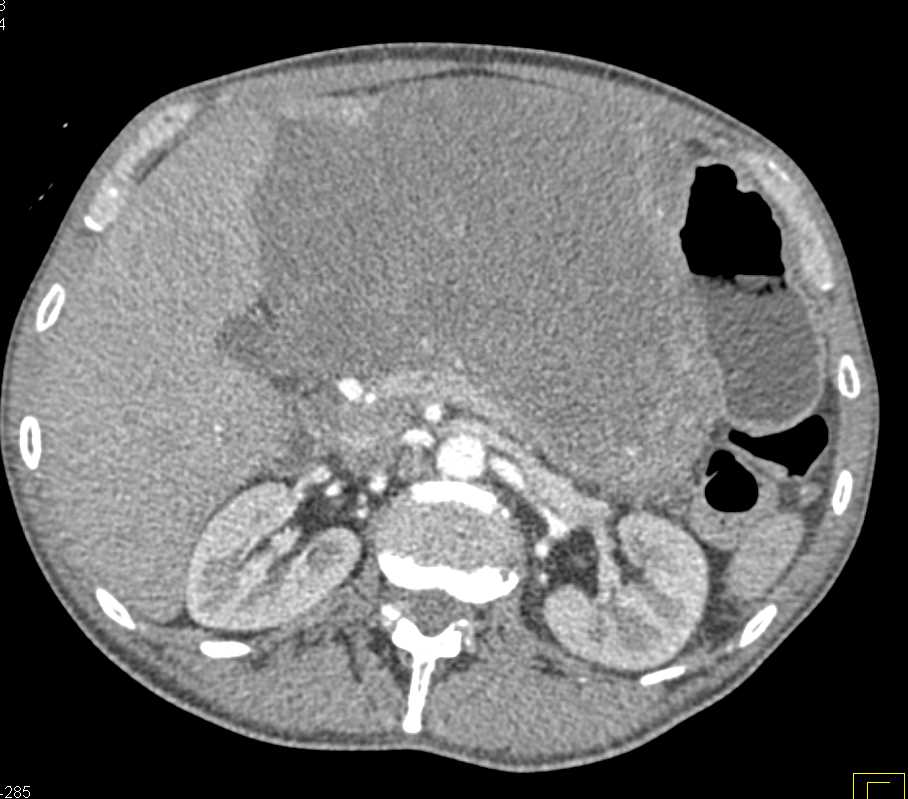

Lagre Gastric GIST Tumor